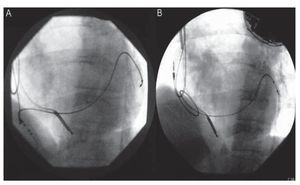

Por la vena femoral derecha se introdujo un catéter de ablación Marinr (Medtronic, Minneapolis, Estados Unidos) en la aurícula derecha a través de una vaina larga SR0 de DAIG (DAIG, St. Jude Medical, Estados Unidos) que se dirigió hasta el SC tras haber introducido la porción distal del catéter de ablación en su porción distal a modo de guía. Retirado el catéter, se realizó una angiografía para reevaluar la anatomía del SC con vistas al recambio (fig. 1). Tras ello, se retiró el sistema a la aurícula derecha y, con la punta del catéter de ablación máximamente curvada, se enganchó el electrodo, y se realizó una ligera tracción de éste hacia la vena cava inferior (fig. 2). El electrodo se movilizó sin dificultad, con desaparición inmediata de la estimulación frénica. El umbral de estimulación final fue de 2,4 V a 0,5 ms. Dada la inminencia del recambio del generador, decidimos no colocar un stent de sujeción, ya que podría dificultar la manipulación del electrodo en el caso de que el resultado obtenido fuese transitorio.

Fig. 2. A: tracción del electrodo. B: posición del electrodo al final de la tracción.